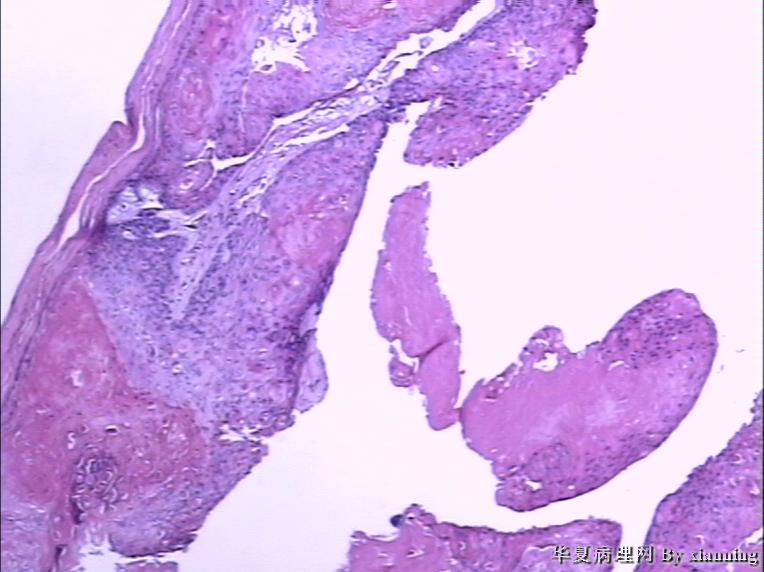

女 50岁 头皮下肿块

巨检:灰白色不规则结节0.9*0.7*0.4cm3,切面灰白色实性质地中等